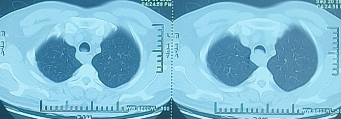

该患者已经间断咳嗽了2年,呼吸困难了2周。2周前患者稍动即喘,至当地医院查胸部CT提示:气管占位,考虑肿瘤性偏恶性可能。当地医院内科抗感染、化痰等保守治疗,效果欠佳,为进一步检查、治疗,来我院。

当地医院胸部CT